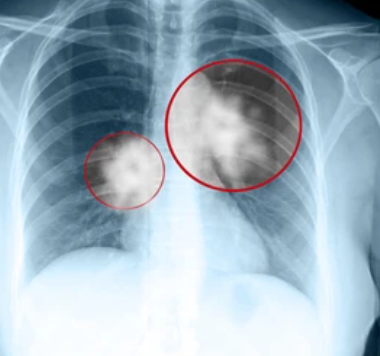

폐암은 폐(레 ungs)에서 발생하는 암의 종류를 가리키는 용어입니다.정확히 말하면,폐암은 폐조직내에서 비정상적인 세포의 증식으로 인해 발생하는 암종류를 의미합니다.

이러한 비정상적인 세포들은 건강한 세포들과 다른특징을 가지며, 암조직을 형성하고 통상적인 폐기능을 정상적으로 활동하지 못하게 합니다.

폐암은 일반적으로 1기~4기로 분류되고, 단계별로 암의 크기와 확산정도에 따라 분석됩니다.